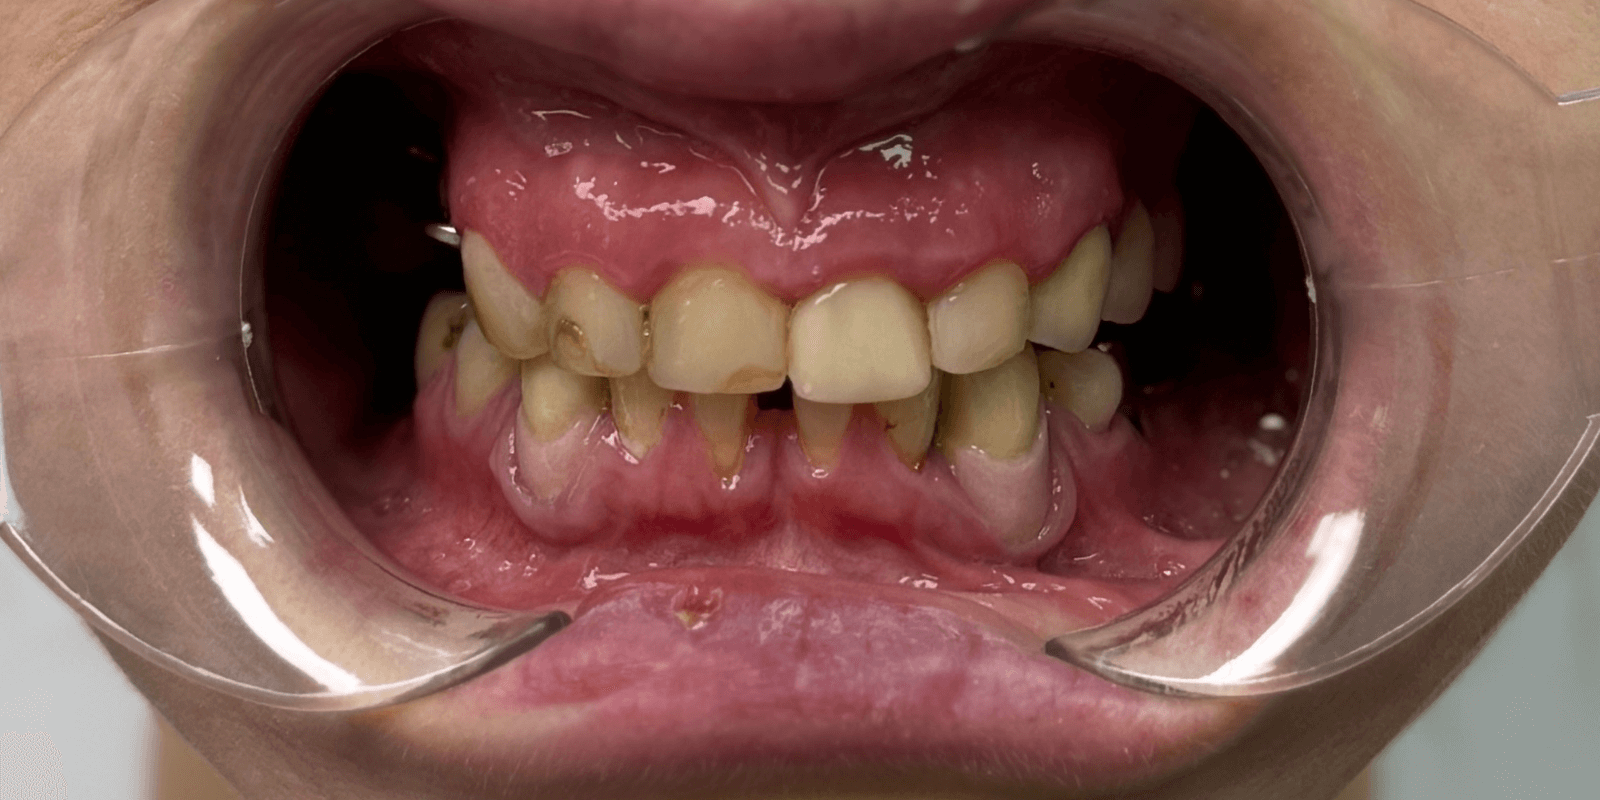

Итог

Мы не просто вылечили зубы. Мы собрали улыбку по частицам, как мозаику — с терпением, заботой и профессионализмом. Женщина, когда-то боявшаяся открыто говорить, теперь смеется с уверенностью. Она вернулась не только к врачу – она вернулась к себе.